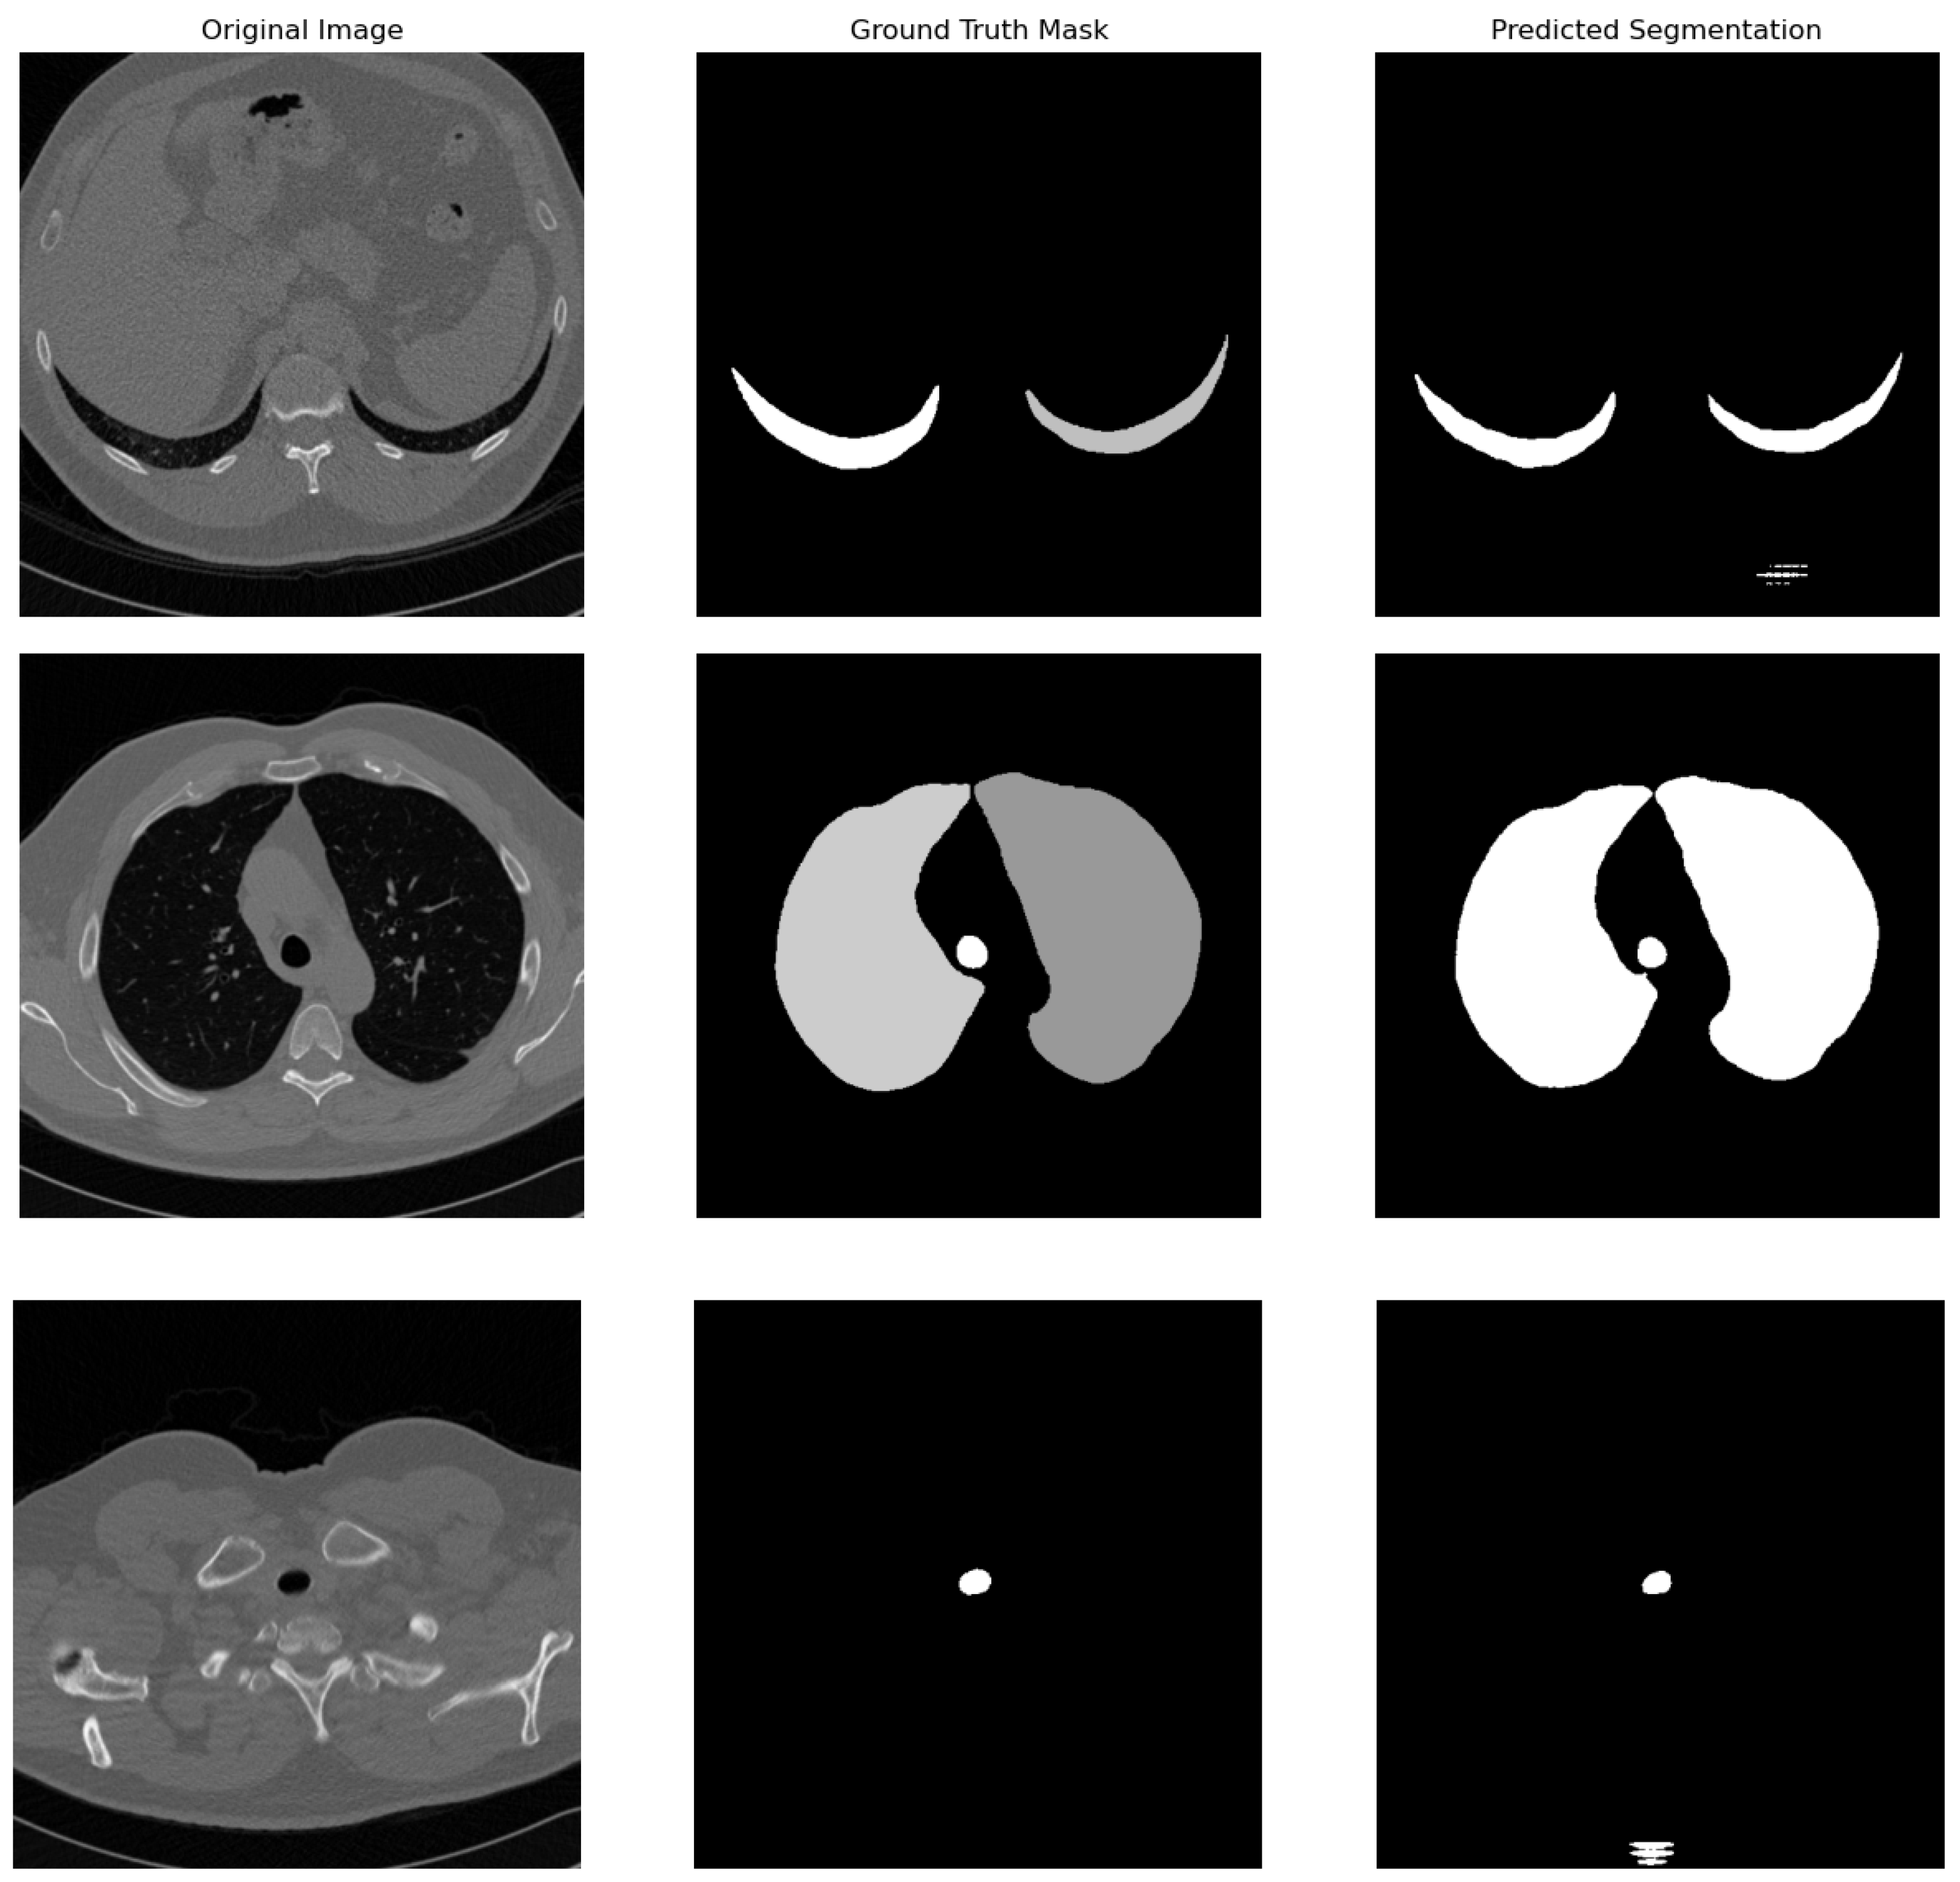

4.2. Qualitative Results